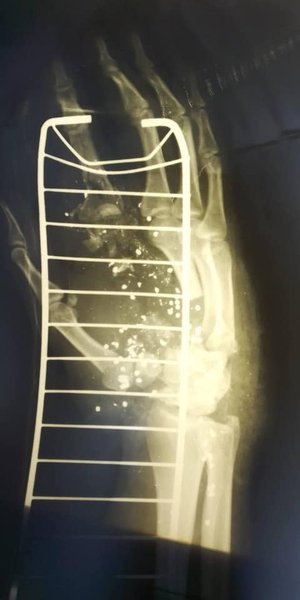

По словам замминистра, сейчас полицейский находится в Национальном институте хирургии и трансплантологии им. Шалимова, где врачи "собирают кости Сергея по частям". Он также опубликовал фотографию конечности, слабонервным ее лучше не видеть.

рентген, сергей василенко, патрульный, киев

Фото: Алексей Белошицкий/Facebook

Замминистра отметил, что огнестрельное ранение патрульный получил из охотничьего ружья, это был выстрел картечью.